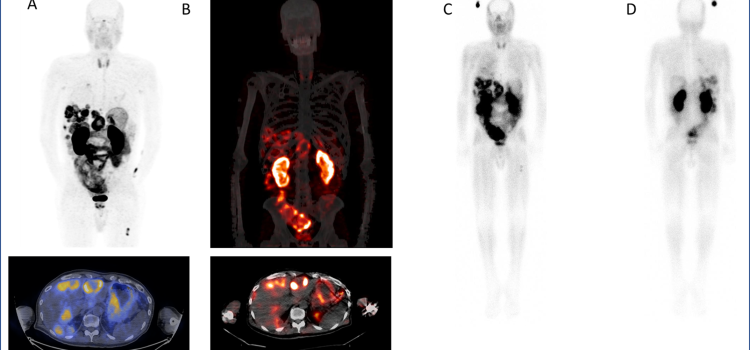

Positron emission tomography (PET) is a nuclear imaging technology (also referred to as molecular imaging) that enables visualization of metabolic processes in the body. The basics of PET imaging is that the technique detects pairs of gamma rays emitted indirectly by a positron-emitting radionuclide (also called radiopharmaceuticals, radionuclides or radiotracer). The tracer is injected into a vein on a biologically active molecule, usually a sugar that is used for cellular energy. PET systems have sensitive detector panels to capture gamma ray emissions from inside the body and use software to plot to triangulate the source of the emissions, creating 3-D computed tomography images of the tracer concentrations within the body.

Precision can have an enormous impact on patients. From diagnosis to patient monitoring (see “How Digital PET/CT Can ...

Analog is approximate. Digital is specific. Therein lies the fundamental difference between digital PET and its analog ...